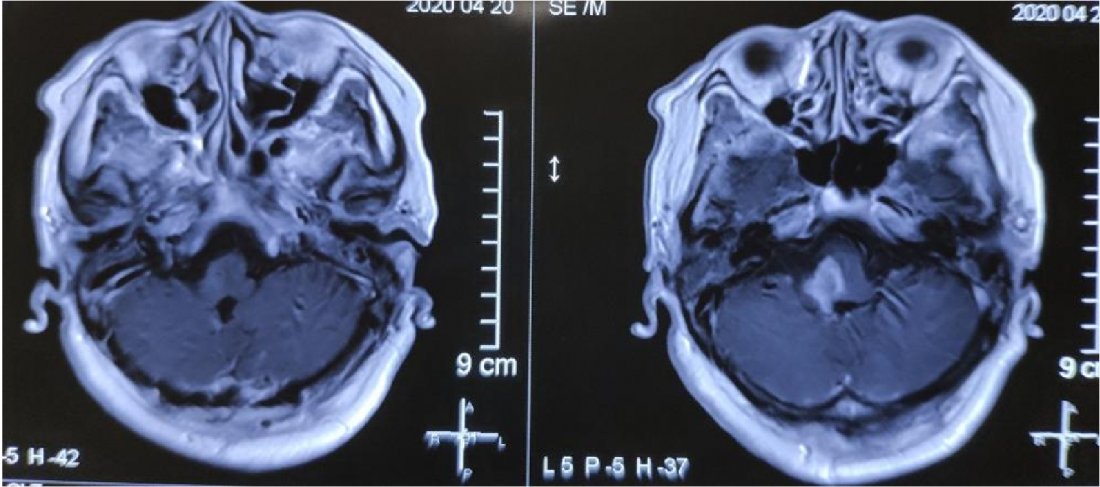

MR显示桥脑右侧高信号影,肿瘤位于四脑室界沟上方之桥脑部分,邻近面丘及动眼神经核,因此患者出现面瘫。

肿瘤位于桥脑与延髓交界处

面神经丘受压明显

术后MR: